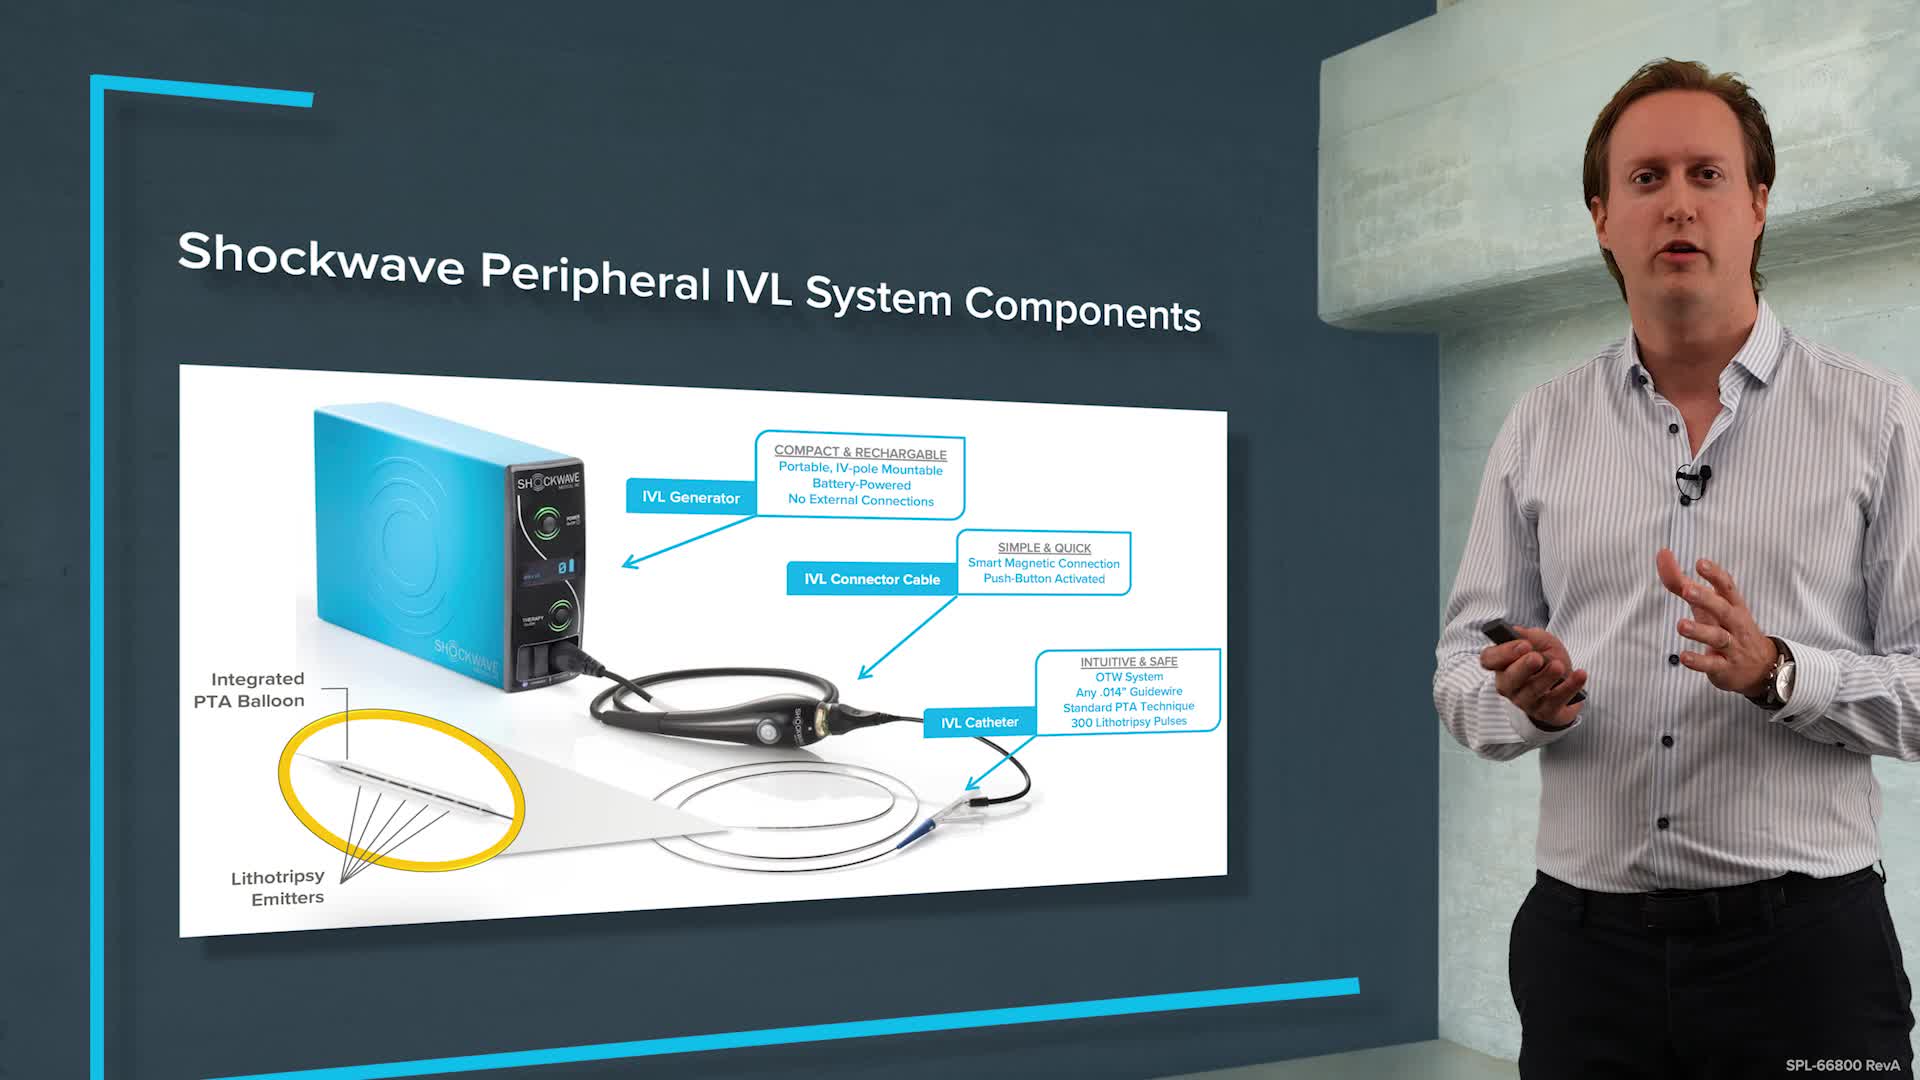

Peripheral IVL learning resources

IVL cracking the calcium conundrum in PAD

Peripheral IVL from the Renals to the Toes